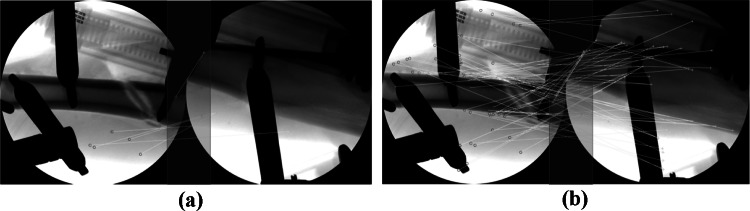

The proposed X-ray image stitching is a heterogeneous approach that includes both integrated feature detection and local image-based estimation. To extract accurate and densely matched features within the overlap region, integrated feature detection was proposed and showed superior performance compared to the conventional feature detections. To verify the effectiveness of integrated feature detection, the locations of the matched features and their pairs were compared (Fig. 5). The red circles and green crosses in each image denote locations of detected features, and the matched features are connected by yellow lines. The red translucent rectangle in the middle of each image denotes the overlap region. The integrated feature detection identified more matched features within the overlap region compared to SIFT feature detection.

Fig. 5.

Comparison of the matched features. (a) Matched features based on conventional feature detection with SIFT. (b) Matched features from the integrated feature detection